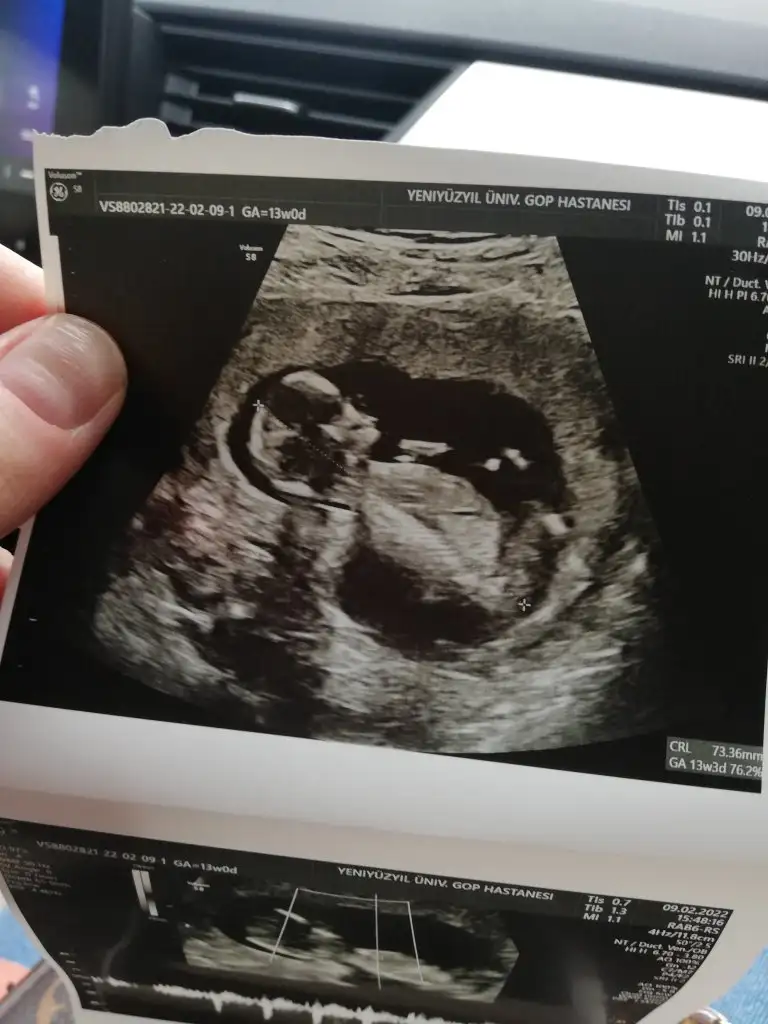

Ikra meyra banada bakar mısınız lütfen nuba göre 13 haftalık bu görüntü yıllar önce bakıyordum buradan bu üçüncü gebeliğim

Eklentiler

• IMG20220209194333.webp